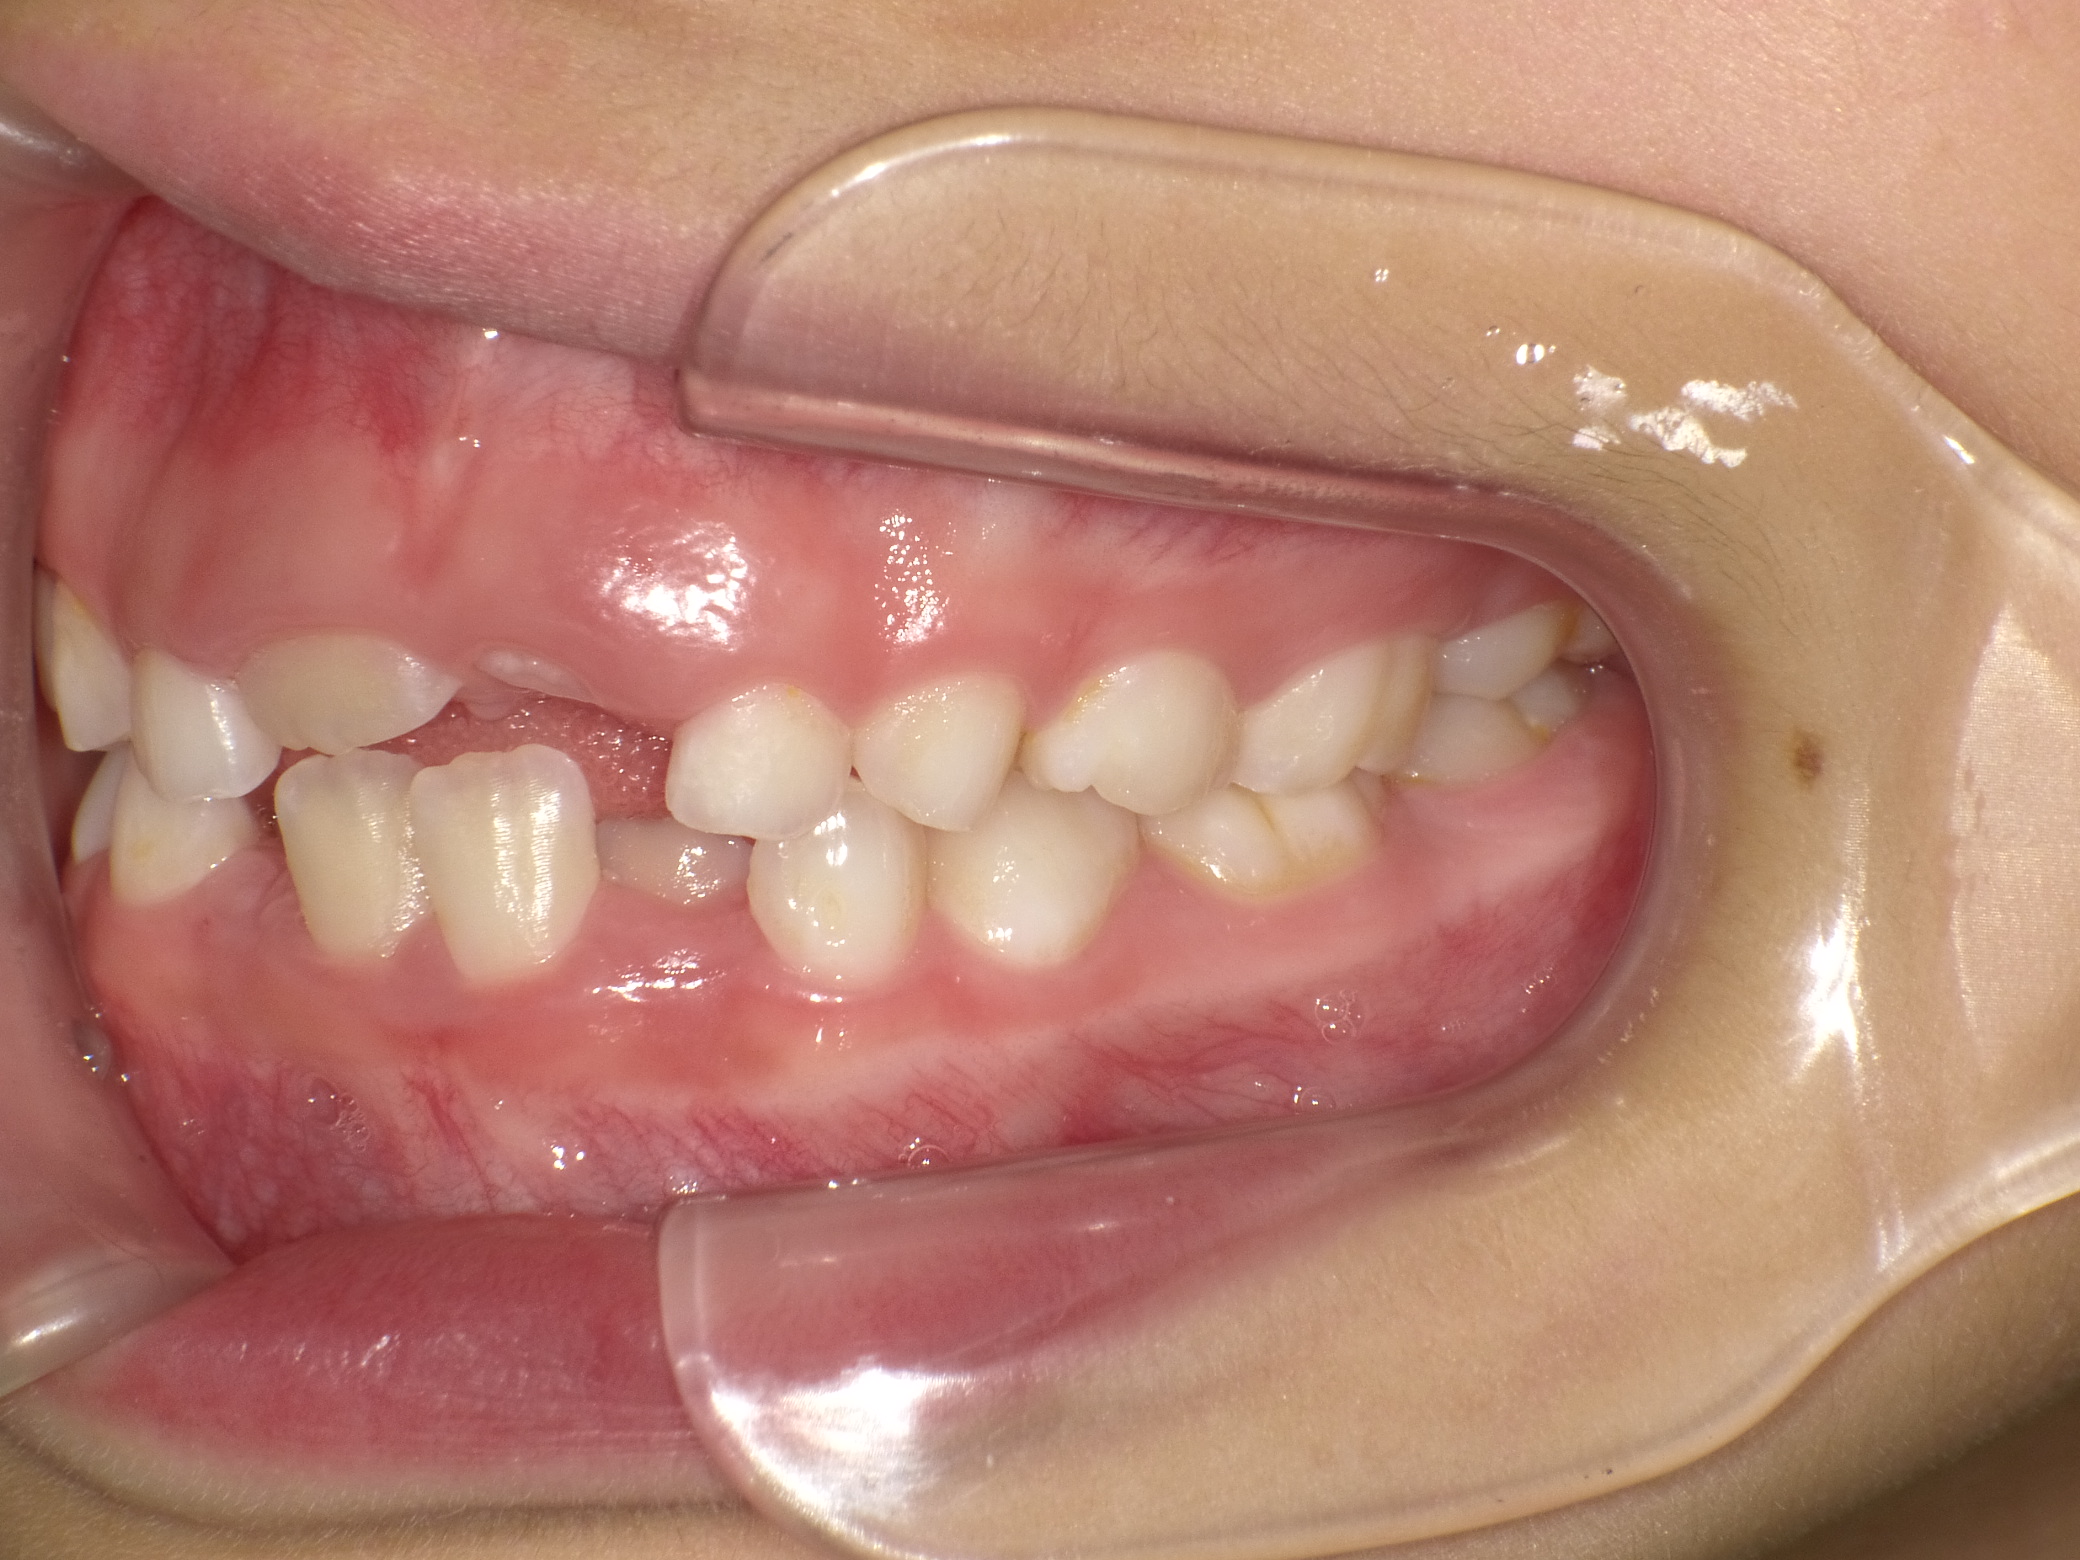

【小学生】 マイオブレース矯正 叢生(でこぼこ)を改善

小学生で開始

マイオブレース

でこぼこ

非抜歯

1期治療のみで改善

Before

After

治療期間

2年

治療開始

8歳

種類

マイオブレース矯正

使用装置

マイオブレース 3Dリンガルアーチ

コメント

非抜歯で 治療期間は2年

治療後4年たっていますが、綺麗な歯並びを維持しています